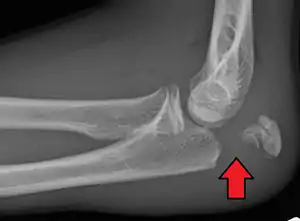

Olecranon fracture

Olecranon fracture is a fracture of the bony portion of the elbow. The injury is fairly common and often occurs following a fall or direct trauma to the elbow. The olecranon is the proximal extremity of the ulna which is articulated with the humerus bone and constitutes a part of the elbow articulation. Its location makes it vulnerable to direct trauma.

To assess an olecranon fracture, a careful skin exam is performed to ensure there is no open fracture. Then a complete neurological exam of the upper limb should be documented.[5][2] Frontal and lateral X-ray views of the elbow are typically done to investigate the possibility of an olecranon fracture.[1] A true lateral x-ray is essential to determine the fracture pattern, degree of displacement, comminution, and the degree of articular involvement.

- Type III: Displaced unstable fracture – In this case, the fracture fragments are displaced and the forearm is unstable in relation to the humerus. It is a fracture -dislocation. It also may be either non-comminuted (Type IIIA) or comminuted (Type IIIB).